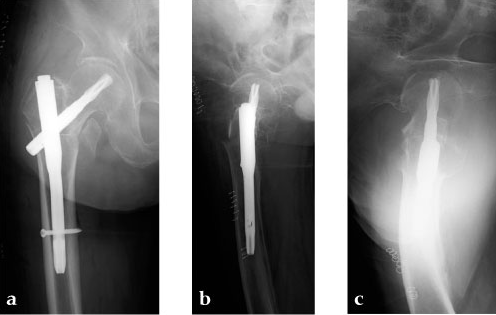

A 78-year-old Japanese patient fell while at her home and sustained an AO 31-A2.1 injury (see Fig 5).

She was operated on the next day and fixed with a PFNA Asia (size: extra small, angle 130 degrees, distal diameter: 9 mm, blade length 100 mm) (Fig 6a). Good reduction and stable fixation were obtained. Full weight-bearing gait was allowed on the second postoperative day. There was an uneventful postoperative course, and good union was obtained at three months after surgery (Fig 6b).